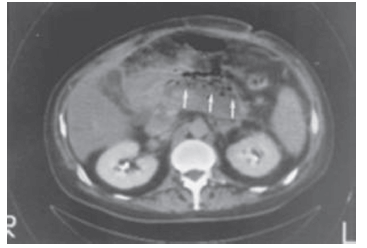

Paciente internado no CTI com pancreatite aguda apresenta piora do quadro e necessita de instalação de aminas vasopressoras. Solicitada uma tomografia abdominal do paciente, a imagem é a seguinte:

A conduta a ser seguida é: